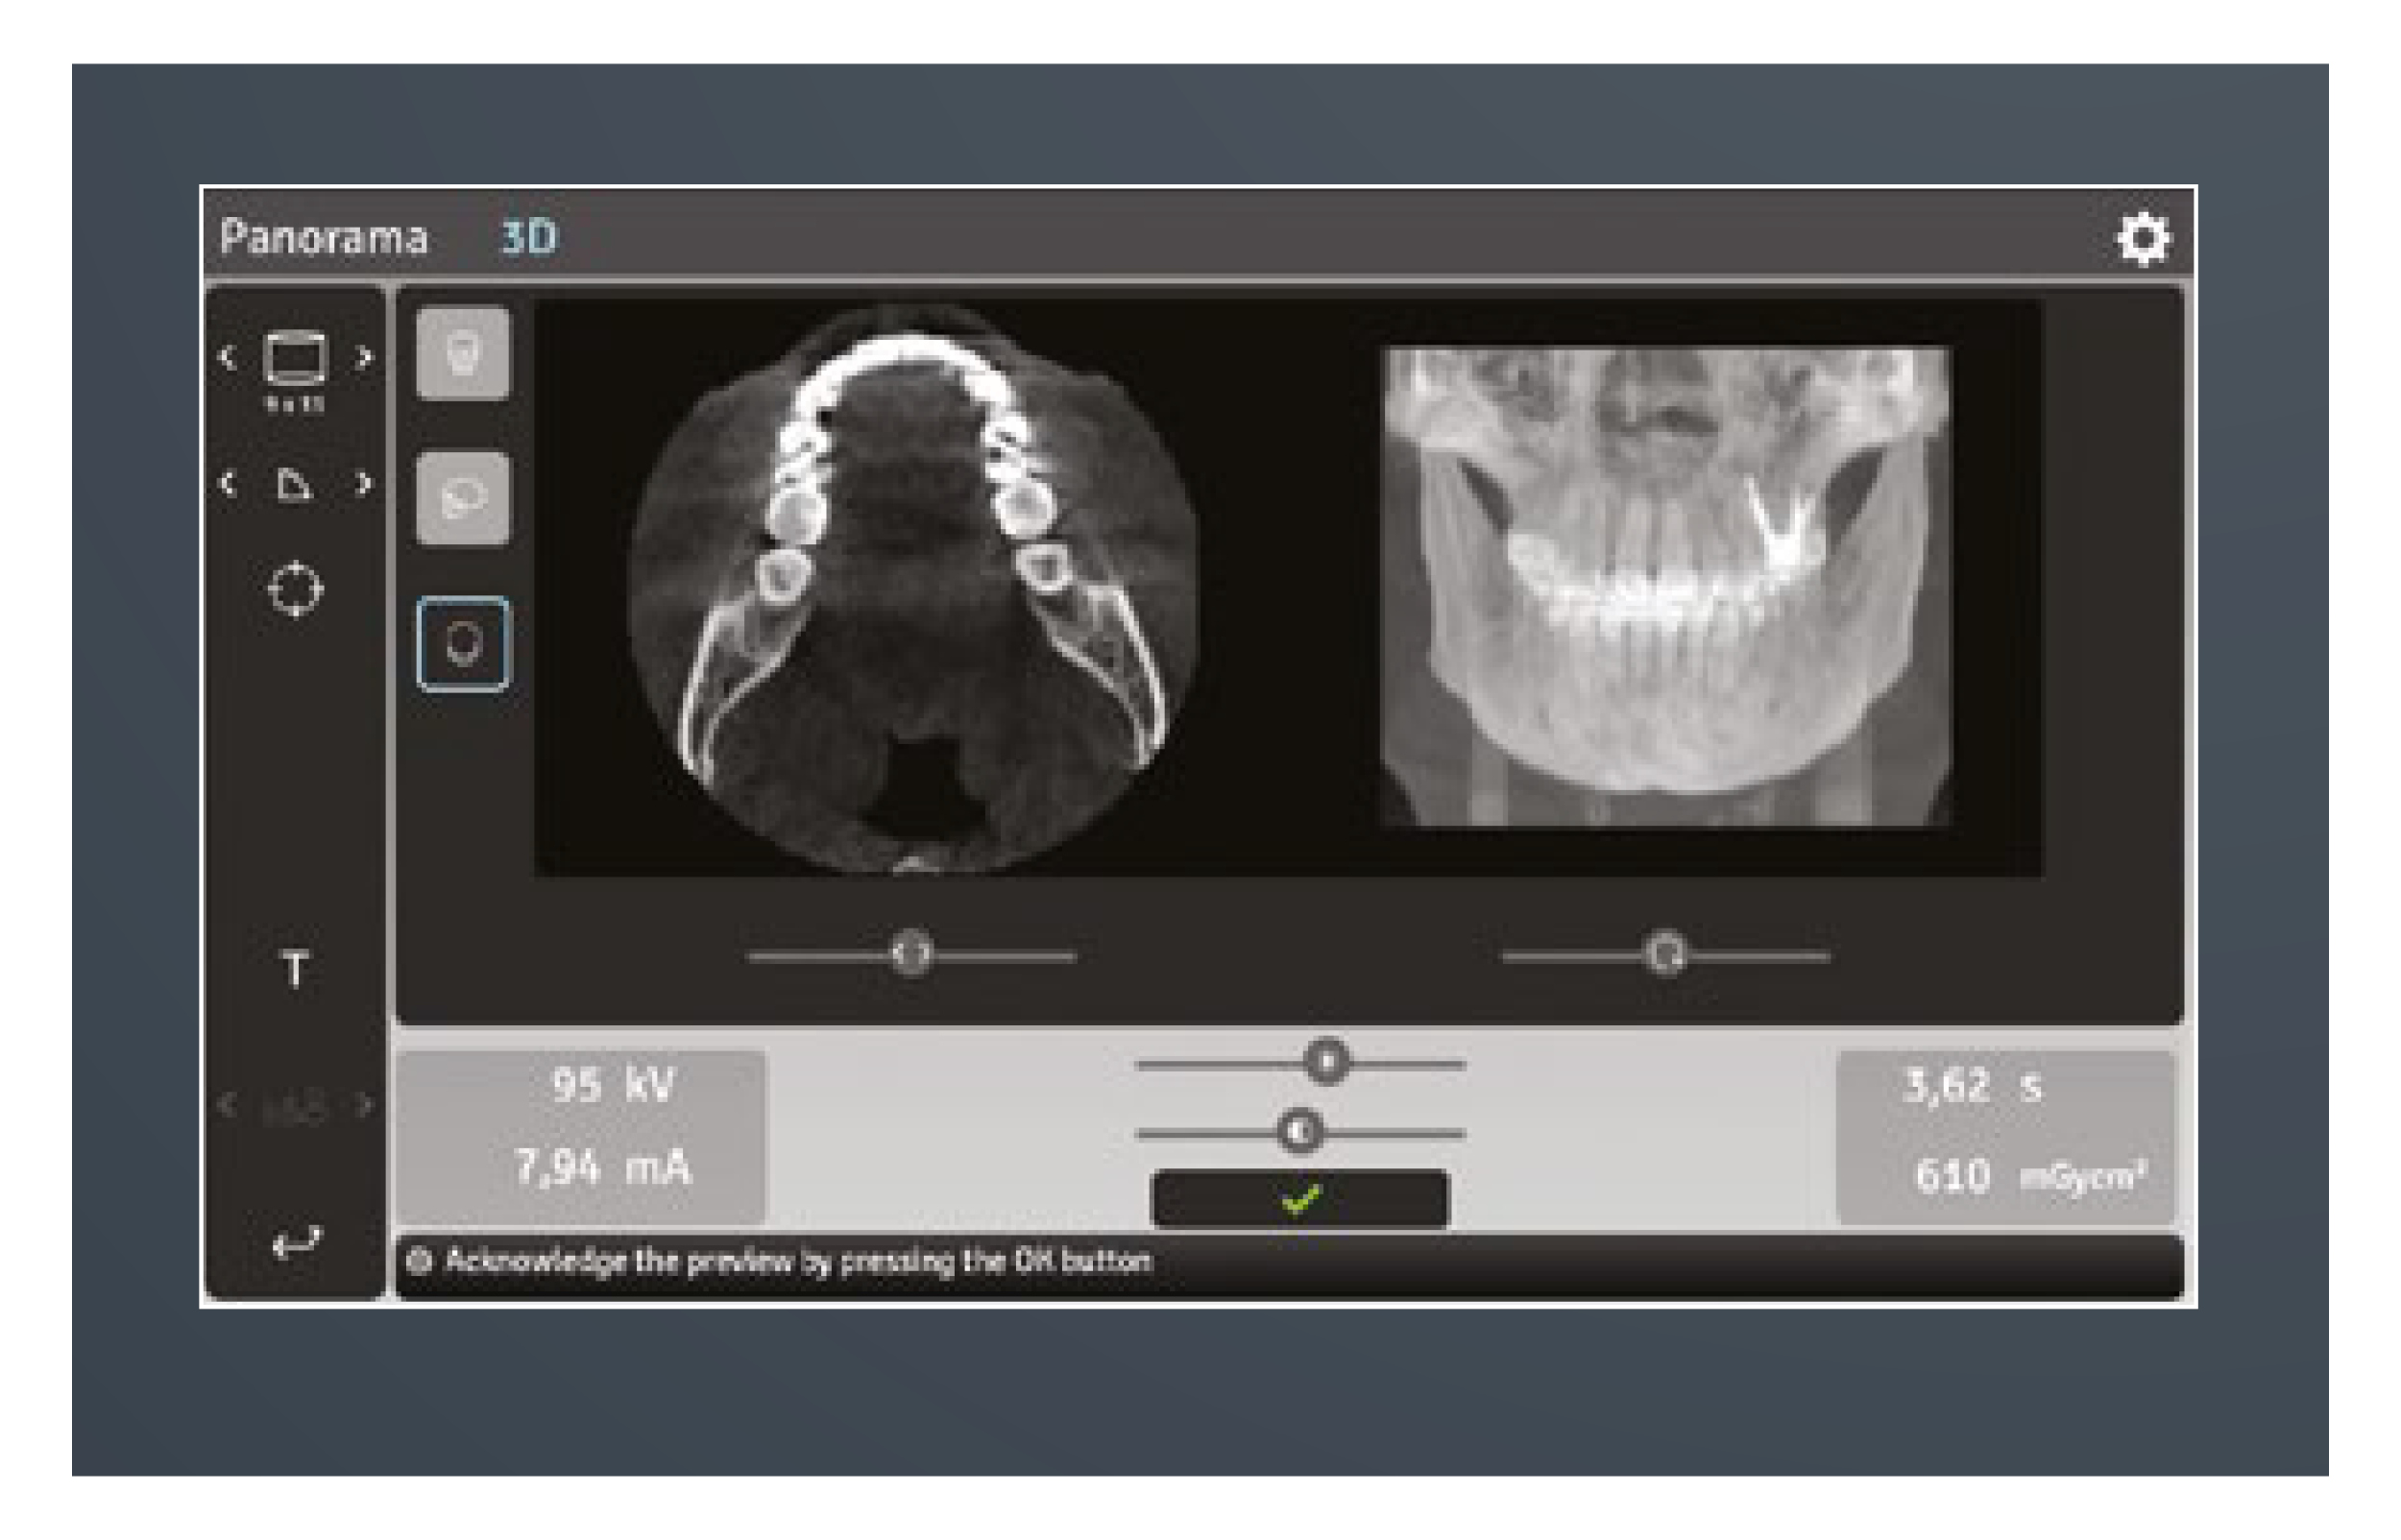

Every feature of the KaVo OP 3D is designed to increase practice efficiency. Preparing the device for a scan is fast with an easy patient positioning system and intuitive graphical user interface. All imaging protocols are optimised for practice workflows.

All functions can be easily and intuitively controlled in a time-saving way via your laptop or PC through the practice’s local network. Only the patient positioning is set on the device.